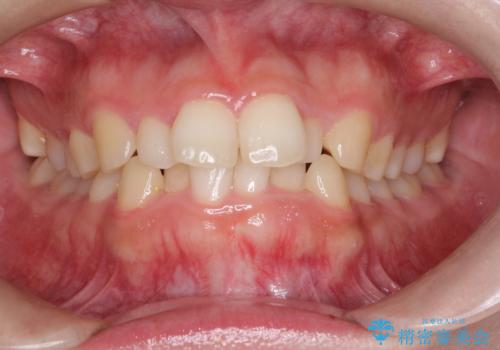

インビザラインでの前歯のガタガタの矯正

- 上下の前歯のがたつきを主訴に来院されました。

歯と歯の間をわずかに削りスペースを作り、インビザラインにて矯正治療を行うこととしました。